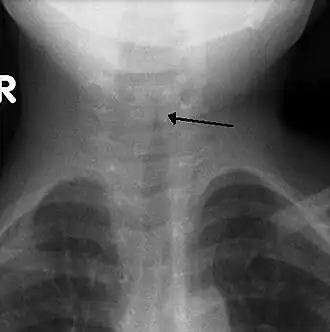

Симптом «остро заточенного карандаша» на рентгенограмме гортани в прямой проекции | |

Может быть информативна рентгенография гортани. У детей с крупом при рентгенографии в боковой проекции может визуализироваться отёк гортаноглотки с сужением подскладочного пространства гортани (в прямой проекции имеющим вид классического симптома «остро заточенного карандаша»)[5].